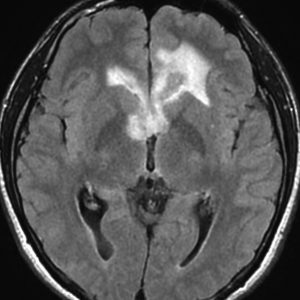

左はICE化学療法 (IFO/CDDP/VP-16)前,右は1コース終了後です。腫瘍は顕著に縮小してgerminomaとして普通の化学療法反応性を示します。また,松果体と下垂体には腫瘍はありません。